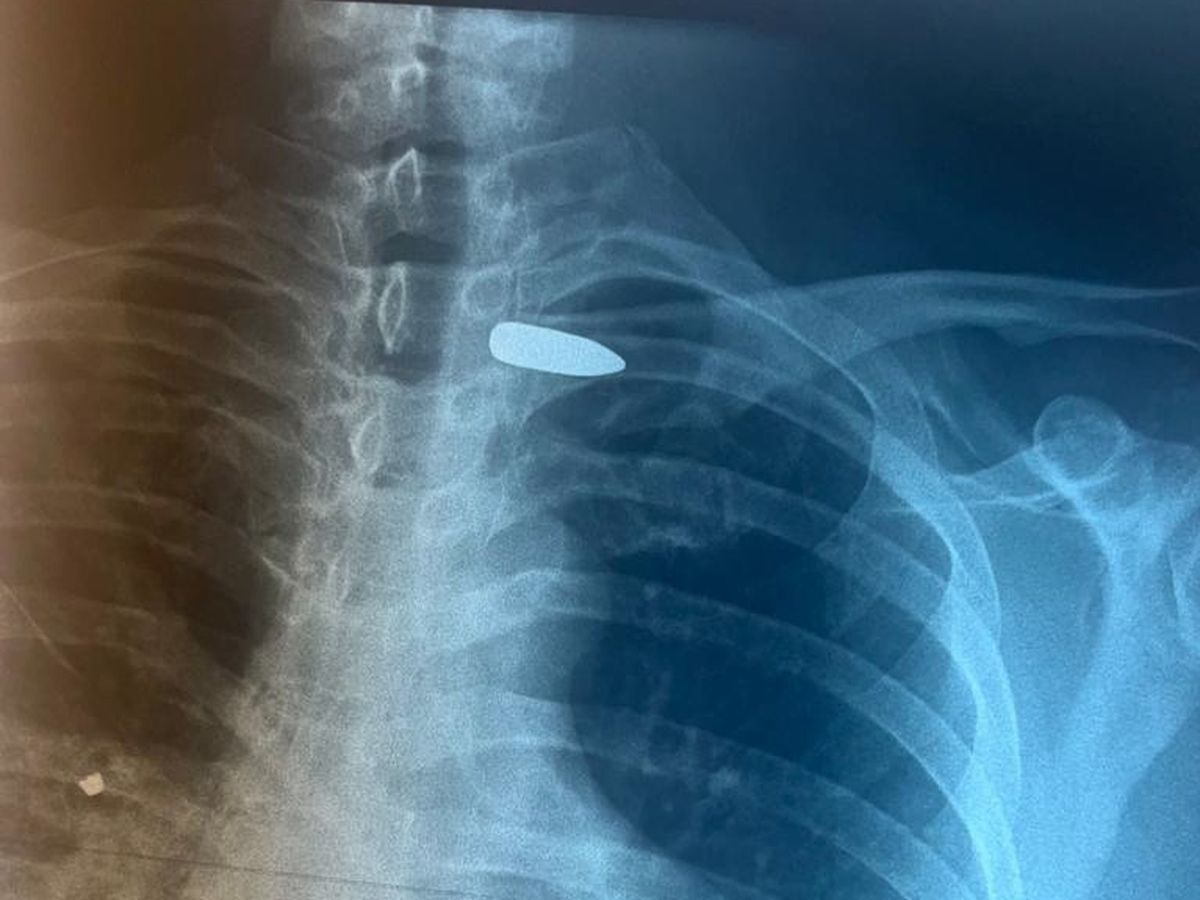

- Вследствие проникающего ранения в правую половину шеи пуля осталась в области сосудисто-нервного пучка в подключичной области слева, - сообщили в медучреждении. - Врачи провели оперативное вмешательство: извлекли пулю из области левой подключичной артерии между ключицей и подключичными сосудами. Операция прошла с применением новейших технологий.

Источник фото: Псковская областная больница